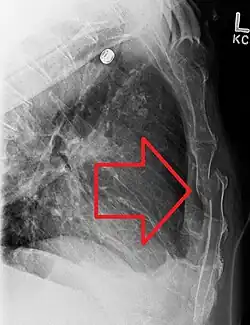

| Sternal fracture | |

| A displaced sternal fracture as seen on plain X-ray | |

Diagnosis

X-rays of the chest are taken in people with chest trauma and symptoms of sternal fractures, and these may be followed by CT scanning.[13] Since X-rays taken from the front may miss the injury, they are taken from the side as well.[14]